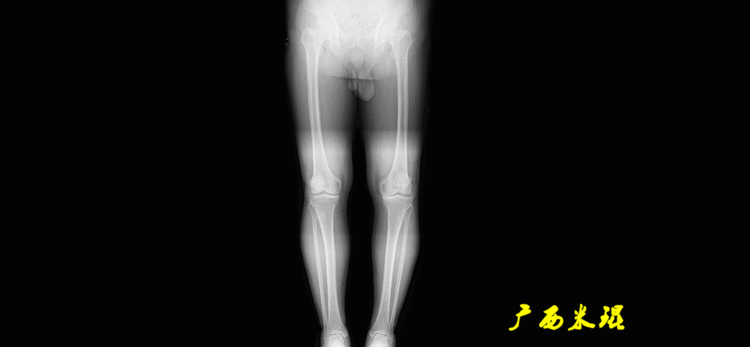

1、确定下肢关节的中心点(1)髋关节中心髋关节中心点由股骨头来确定,由于股骨头是相对比较规则的圆形,使用Mose圈或圆规就能确定股骨头中心也就是髋关节中心。

(2)膝关节中心膝关节中心点常用的有5个不同的定位方法,分别是股骨髁中点、股骨髁间窝顶点、膝关节间隙水平软组织中点、胫骨髁间嵴中点和胫骨平台中点,我们可以根据具体情况来选用。

(3)踝关节中心踝关节中心点常用的也有3个,分别是骨骼(内、外踝表面间距)中点、踝关节间隙水平软组织中点和距骨宽度中点。

2、画出下肢的轴线确定髋关节、膝关节、踝关节的中心点后,我们才能了解下肢的几个轴线。(1)解剖轴股骨和胫骨的骨干中线为解剖轴,股骨解剖轴和胫骨解剖轴的夹角正常值为174°±1°。